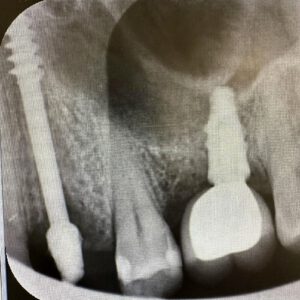

1. Radiología 3D de alta precisión.